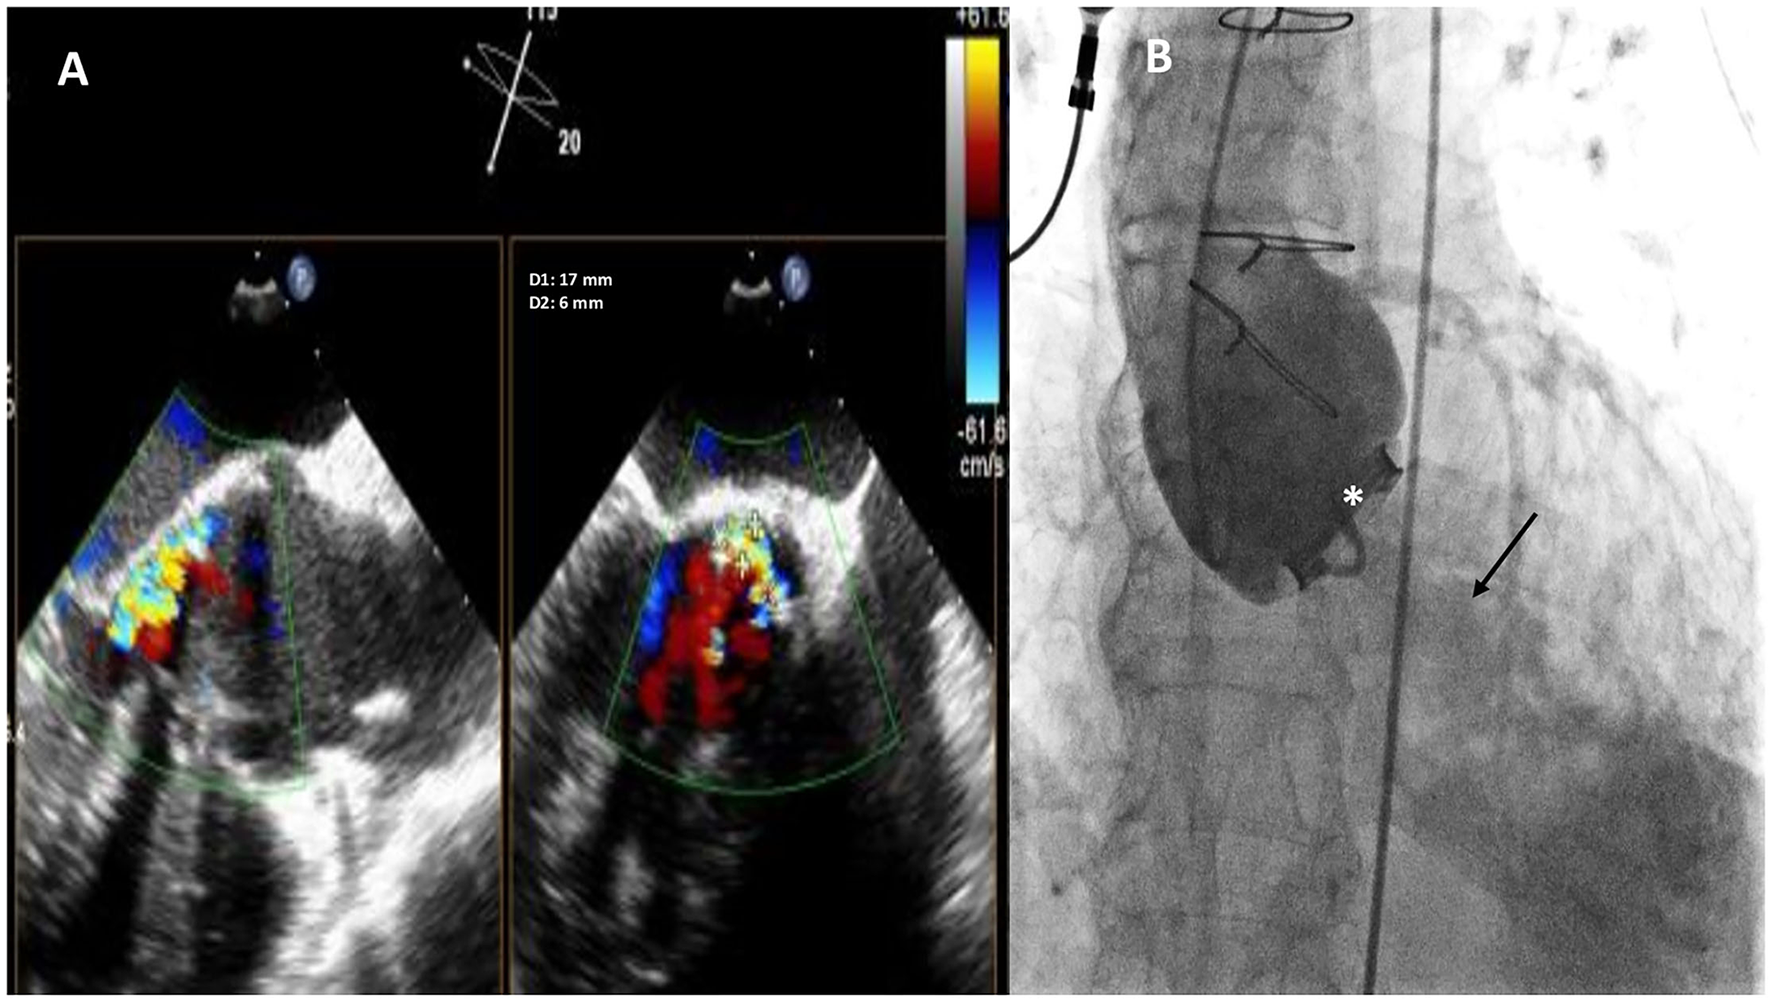

Figure 1

Baseline two-dimensional (2D) X-plane imaging Transoeophageal Echocardiogram (TEE) color Doppler (A) and ascending aorta angiography (B) showing the presence of a huge crescent-shaped 17 × 6 mm aortic PVL located at non coronary cusp (NCC) 9-12 o'clock, with moderate-to-severe regurgitation. Fluoro-angiographic image confirming the stable position of the mechanical tilting disc aortic prosthetic valve (white asterisk) with moderate regurgitation (black arrow).